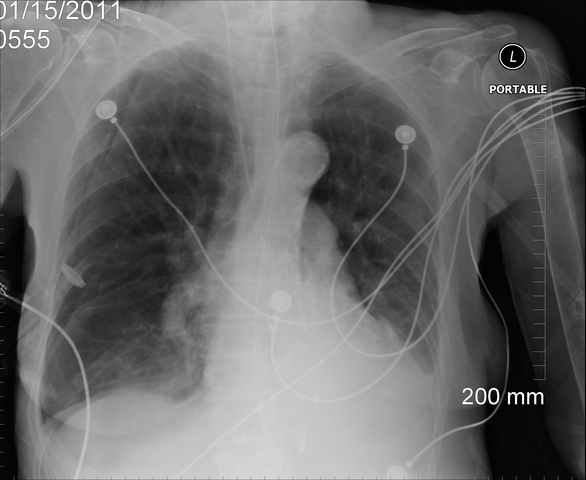

CXR revealed peristent infiltrates throughout each lung significant with Pneumonia. This would explain the increased WBC count. Potassium levels were back to normal and potassium was discontinued. ABG revealed a compensated metabolic alkalosis mild hypoxemia. Vent changes ordered to PSV with a RR of 5, PEEP of 5 cmH2O one hour BID as tolerated. Failed and switched back to previous settings.

CXR revealed emphysema and possible right basilar atelectasis. Sedation discontinued and PS decreased to 12. ABG revealed a partiall compensated metabolic alkalosis with mild hypoxemia. Dr. Knowall ordered her to be extubated once awake and if fails possibly a trach will be performed. CHF had improved. CXR showed worsening of inifiltrates on top of the emphysema and bibasilar atelectasis. Did well once extubated. Treatments and antibiotics continued.